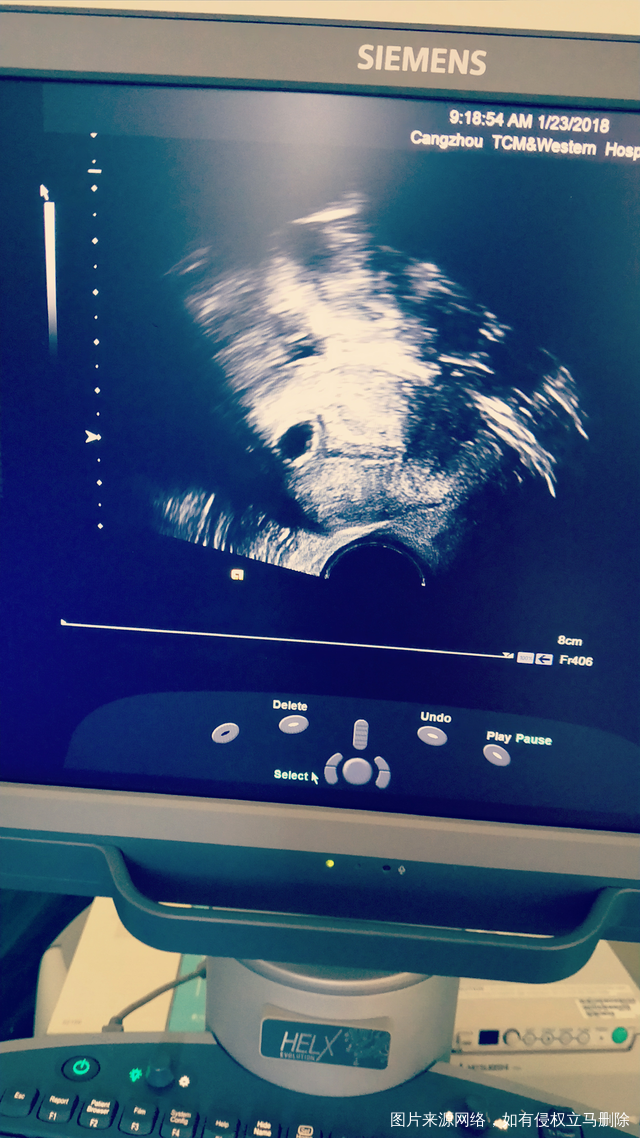

冻囊胚第33天做的复查,帮我看看有胎芽吗?从0.6乘0.5吃了八天的药复查才长到0.9乘0.8,一直在就褐色,今天就流血了